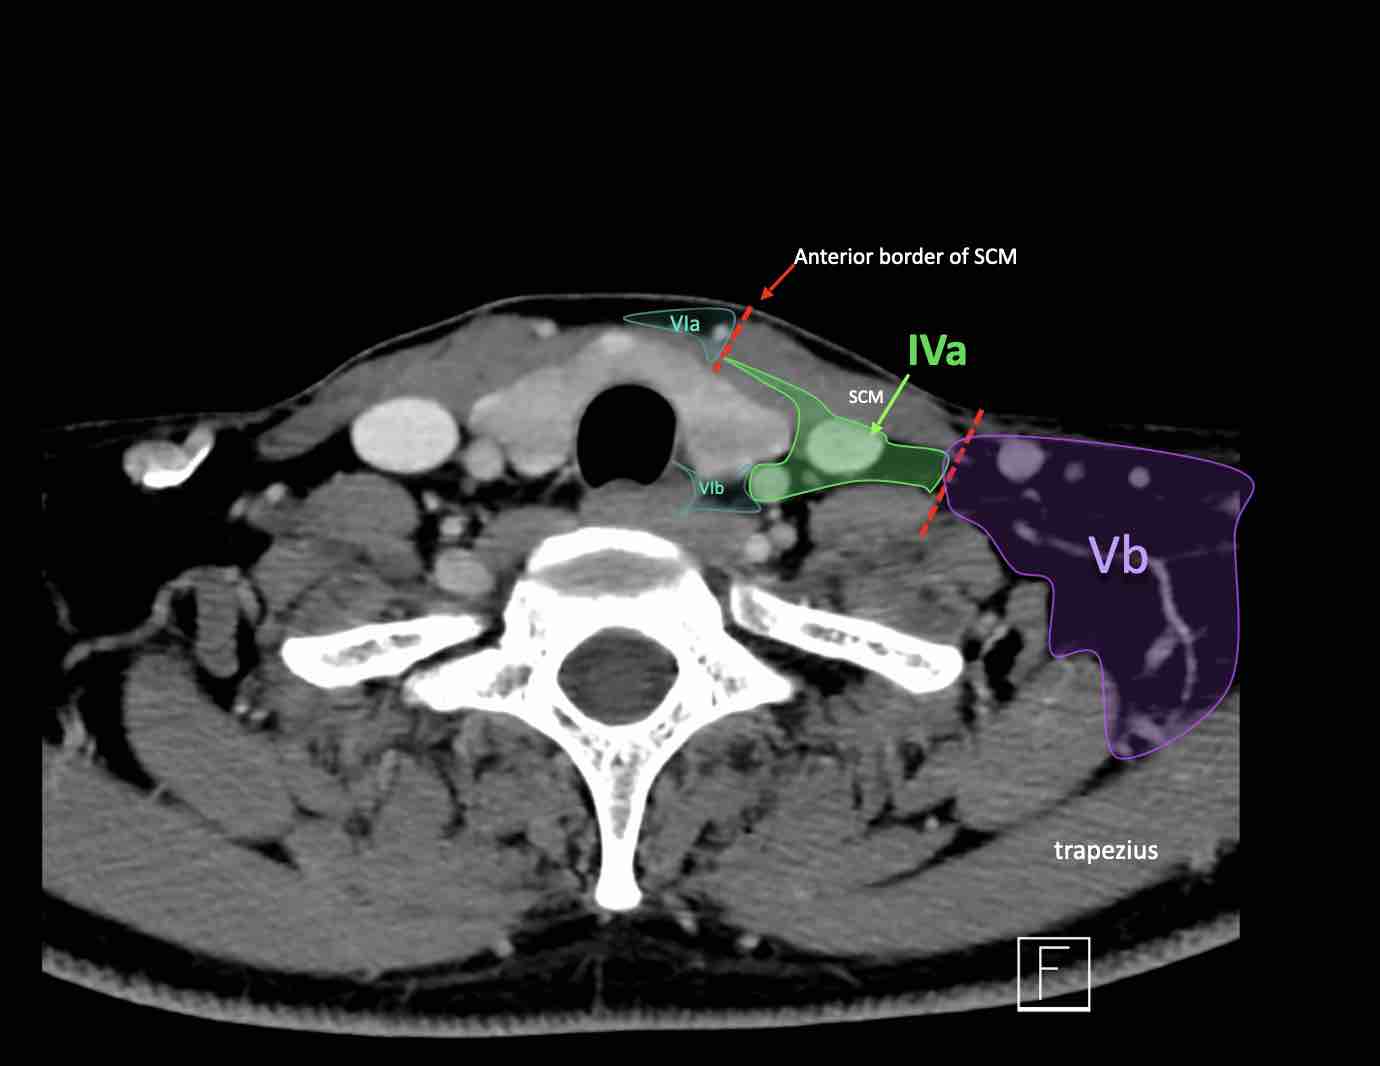

IV – Tĩnh mạch cảnh dưới và hố thượng đòn trong

Tầng IVa

Các hạch này có nguy cơ chứa di căn từ các ung thư hạ hầu, thanh quản, tuyến giáp và thực quản cổ.

Hiếm gặp hơn, di căn từ khoang miệng trước có thể biểu hiện tại vị trí này với tổn thương hạch gần tối thiểu hoặc không có.

V – Tam giác cổ sau và hố thượng đòn

Tầng V chứa các hạch của nhóm tam giác cổ sau nằm ở phía sau cơ ức đòn chũm, xung quanh phần dưới của thần kinh phụ gai sống và các mạch máu cổ ngang.

Tầng Vc – Hố thượng đòn

Tầng này chứa các hạch thượng đòn bên nằm trong phần tiếp nối của các hạch tam giác cổ sau (tầng Va và Vb) từ các mạch máu cổ ngang xuống đến giới hạn được xác định tùy ý tại vị trí 2 cm phía trên cán ức.

Tầng này tương ứng một phần với vùng được gọi là hố thượng đòn.

Tầng Vc nhận các bạch mạch hướng tâm từ các hạch tam giác cổ sau (tầng Va và Vb) và thường liên quan hơn đến các khối u vòm hầu [1].